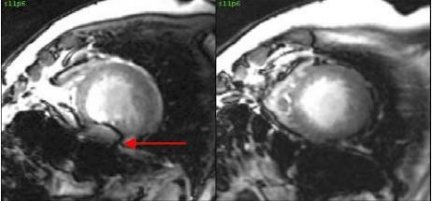

4. Place the parallel slices or single slice over the area of interest.

• To optimize the gated 2D FIESTA prescan enhancement, the intersection of the shim volume and slice locations should only be placed over the anatomy of interest.

Figure 2. Correct intersection and placement of shim volume and slice locations

Figure 3. Incorrect intersection and placement of shim volume

Figure 6. Reduced susceptibility artifact (right image)

Figure 7. Off-resonance artifact at 3.0T (left) and reduced artifact (right)